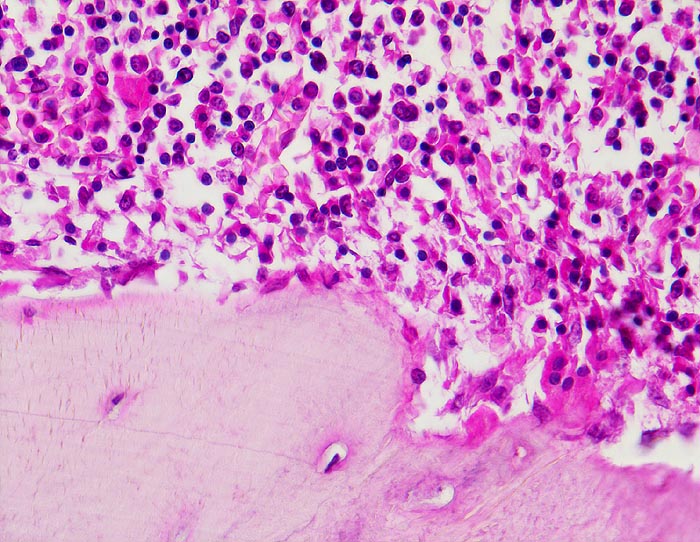

Normale Spongiosa

Normale Spongiosa mit Osteoblasten an der Bälkchenoberfläche und blutbildendem Mark. Bei der mehrkernigen Riesenzelle rechts unten im Bild handelt es sich um einen Osteoklasten.